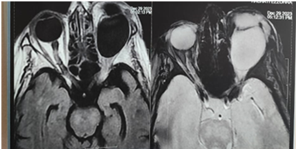

Imaging (CT and MRI)

revealed a cystic lesion of the superior-internal angle of the left orbit,

measuring 29x 20 x 17 mm, at the thin-walled level of the medial rectus muscle,

pushing the eyeball and nerve outwards and causing grade I exophthalmos.